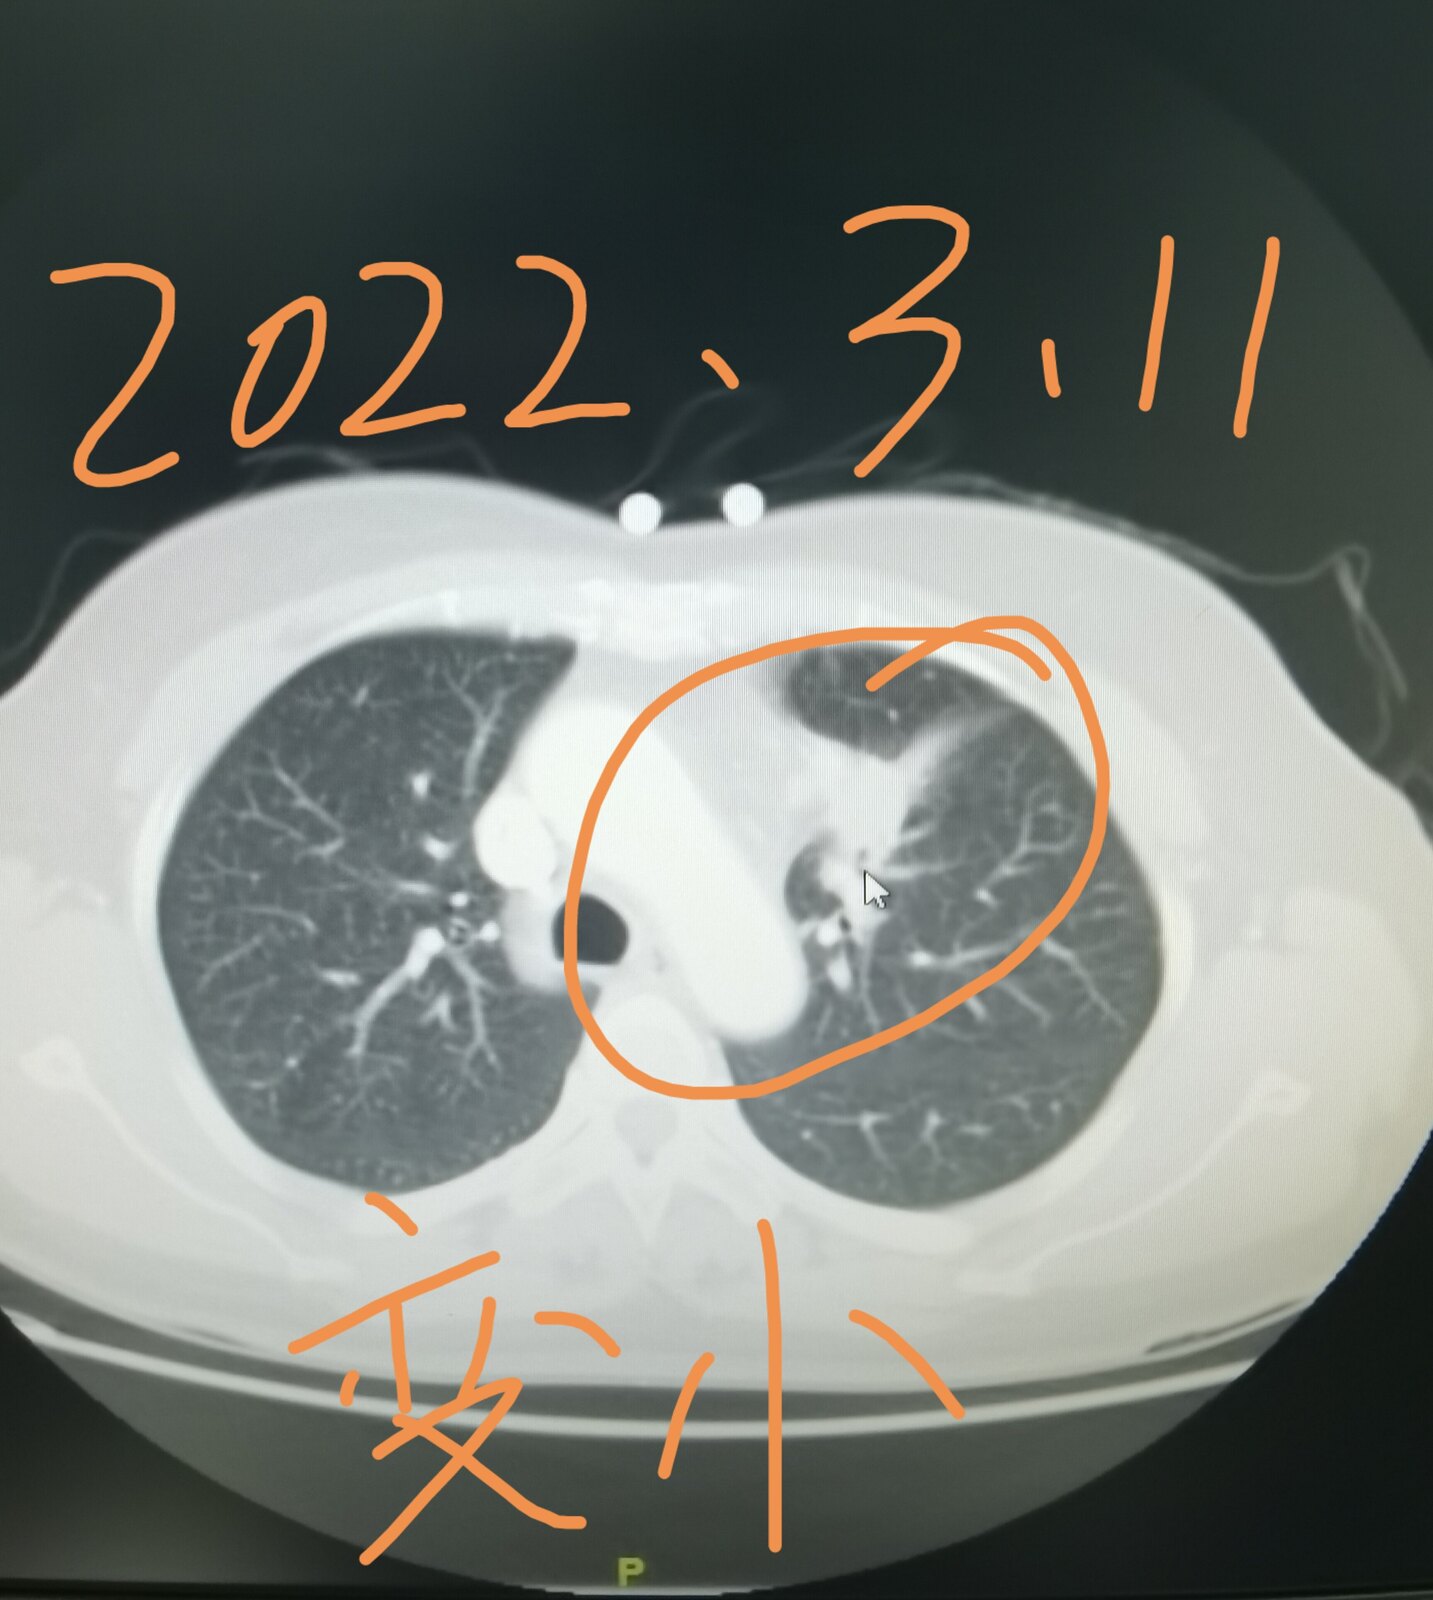

今天有一台手术就属于这个情况,我把这位患者的片子给大家发在下面,这是一位51岁的女士,三个月前因为咳嗽在当地医院拍片子,发现了肺部占位,她过来找我,想在我这里治疗。我给她进行了系统的检查,当时发现左上肺这个占位侵犯了纵隔,纵隔淋巴结增大,考虑转移,直接手术效果不好。这位女士好在其他部位并没有转移,我给她安排了穿刺,病理显示是一个肺腺癌,做基因检测,存在EGFR敏感突变,她吃了两个月的靶向药,肿瘤和淋巴结都缩小了。今天给她做的手术,手术过程是很困难的,里边粘连的比较严重,血管也很难分离,但过程很顺利,现在正在密切观察中。她除了左上肺这个病变之外,左下肺还有一个结节,吃靶向药也没有减小,术中探查的时候,考虑是一个肺内淋巴结,也给她一并切了下来。

通过这个病例我们知道,有些局部晚期肺癌,通过吃靶向药使肿瘤缩小,仍然有手术机会,并且效果会更好。